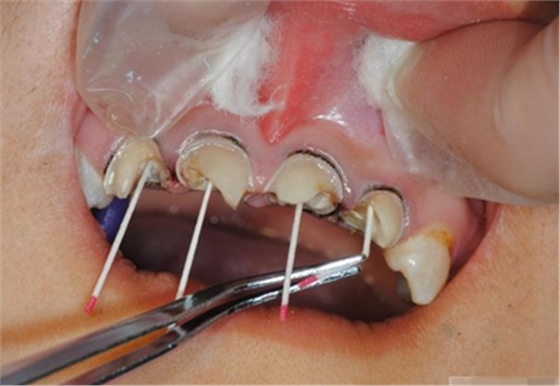

【纖維樁制作】

Hawe Sycamore Interdental Wedges——小楓木

切忌在近遠(yuǎn)中同時(shí)放置楔子,這樣會(huì)擠壓牙齒使其伸長,調(diào)合時(shí)會(huì)感覺修復(fù)體過高。如果近遠(yuǎn)中需要修復(fù)時(shí),可在一端放置楔子,修復(fù)后,再放置另一端

修整纖維樁長度

取出纖維樁,按所需長度裁截纖維樁 在有水條件下 用切割砂片或車針截取纖維樁,切勿使用鉗子,剪刀或鑷子以免破壞樁的結(jié)構(gòu)